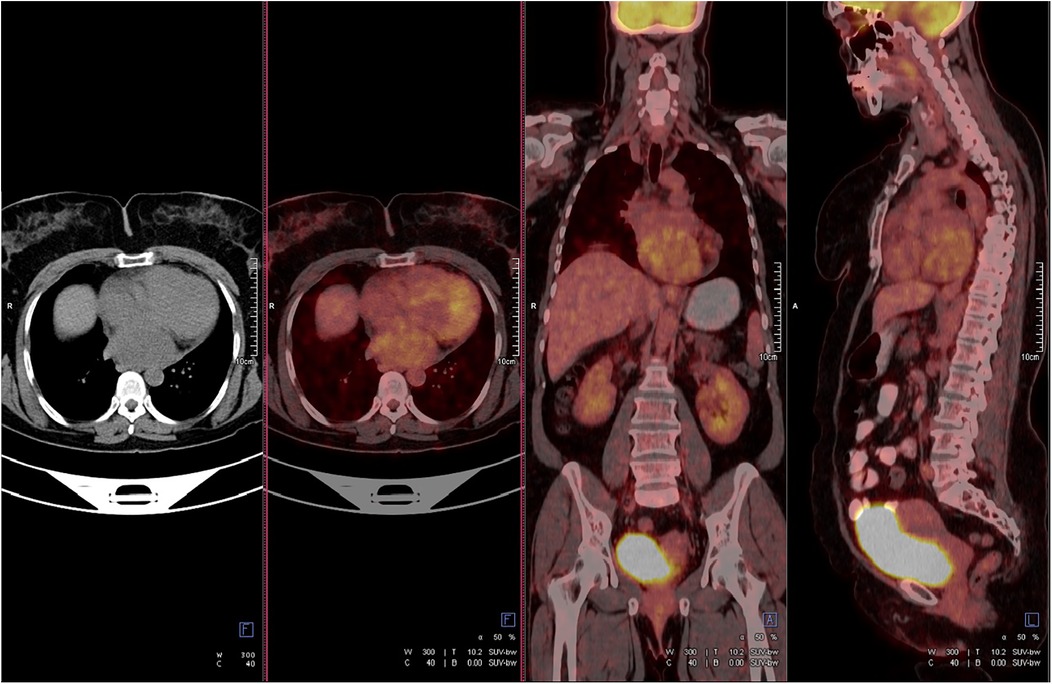

A 47-year-old female patient applied to the cardiology outpatient clinic with complaints of exertional dyspnea and intermittent chest pain. The patient's New York Heart Association (NYHA) functional capacity score was 2–3. Chest pain was unrelated to exertion. The patient had hypertension and was normotensive under perindopril 10 mg and amlodipine 10 mg treatments. She was a nonsmoker and had Class I obesity with a body mass index of 30.8 kg/m2. Physical examination was normal. Laboratory parameters showed an elevation of low-density lipoprotein at 187 mg/dl and an elevation of N-terminus pro-B-type natriuretic peptide (NT-proBNP) at 684 pg/ml. The electrocardiogram showed sinus rhythm with a rate of 83 bpm and no abnormalities. Transthoracic echocardiography (TTE) revealed a well-circumscribed hypoechoic mass lesion measuring 8.5 cm × 5.4 cm, located behind the posterior walls of the left atrium and left ventricle, causing significant compression of the left atrium (Figures 1A,B). Other findings of TTE were; normal left ventricular systolic function with a left ventricular ejection fraction (LVEF) of 65%, mild dilatation of the left atrium with a left atrial volume index (LAVI) of 36 ml/m2, mild mitral valve regurgitation, mild tricuspid valve regurgitation, tricuspid valve regurgitation velocity 3.2 m/s, grade II diastolic dysfunction and normal right ventricular systolic function with a tricuspid annular plane systolic excursion of 22 mm. Transesophageal echocardiography (TEE) was performed for detailed evaluation of the mass and its neighbors. TEE showed a mass containing a cystic lesion that caused significant compression of the left atrium (LA) and mild compression of the inferior vena cava (IVC) (Figure 2). No pulmonary venous return anomaly or obvious compression of the pulmonary veins was detected on TEE. Thoracic computed tomography (CT) angiography revealed a pericardial mass lesion measuring 10.1 cm × 8.1 cm × 5.2 cm in size, with regular borders and soft tissue density, located in the posterior mediastinum, adjacent to the LA and descending aorta, creating significant compression on the esophagus (Figure 3). The whole-body 18F-fluorodeoxyglucose (18F-FDG) positron emission tomography (PET)-CT images revealed a giant pericardial mass with mild to moderate 18F-FDG avidity (Figure 4). No metastatic lesions were detected. Magnetic resonance imaging (MRI) showed a well circumscribed, T1-hypointense and T2-hyperintense pericardial mass. The mass was observed to have homogeneous signal intensity on T1 and T2-weighted images. There was no direct myocardial infiltration and/or left atrial invasion (Figure 3). Contrast-enhanced images were not obtained for the patient who had a history of anaphylactic shock due to a gadolinium-based contrast agent. CT and MRI showed that the mass did not cause myocardial involvement, however, the mass could not be demarcated from the LA and IVC. The coronary angiogram did not detect obstructive coronary artery disease or coronary artery compression due to the mass. For the histological diagnosis of this giant pericardial mass, EUS-FNA was performed. Histological evaluation revealed foci of spindle cell proliferation forming Antoni A and Antoni B areas. Immunohistochemical studies revealed that these spindle cells stained diffusely positive for S100, which was consistent with schwannoma. The Ki-67 index was less than 1%.

Figure 4

Figure 4. Positron emission tomography-computed tomography showed mild to moderate fluorodeoxyglucose uptake in the mass. The standard uptake value was ∼5.2. No metastatic lesions were detected.